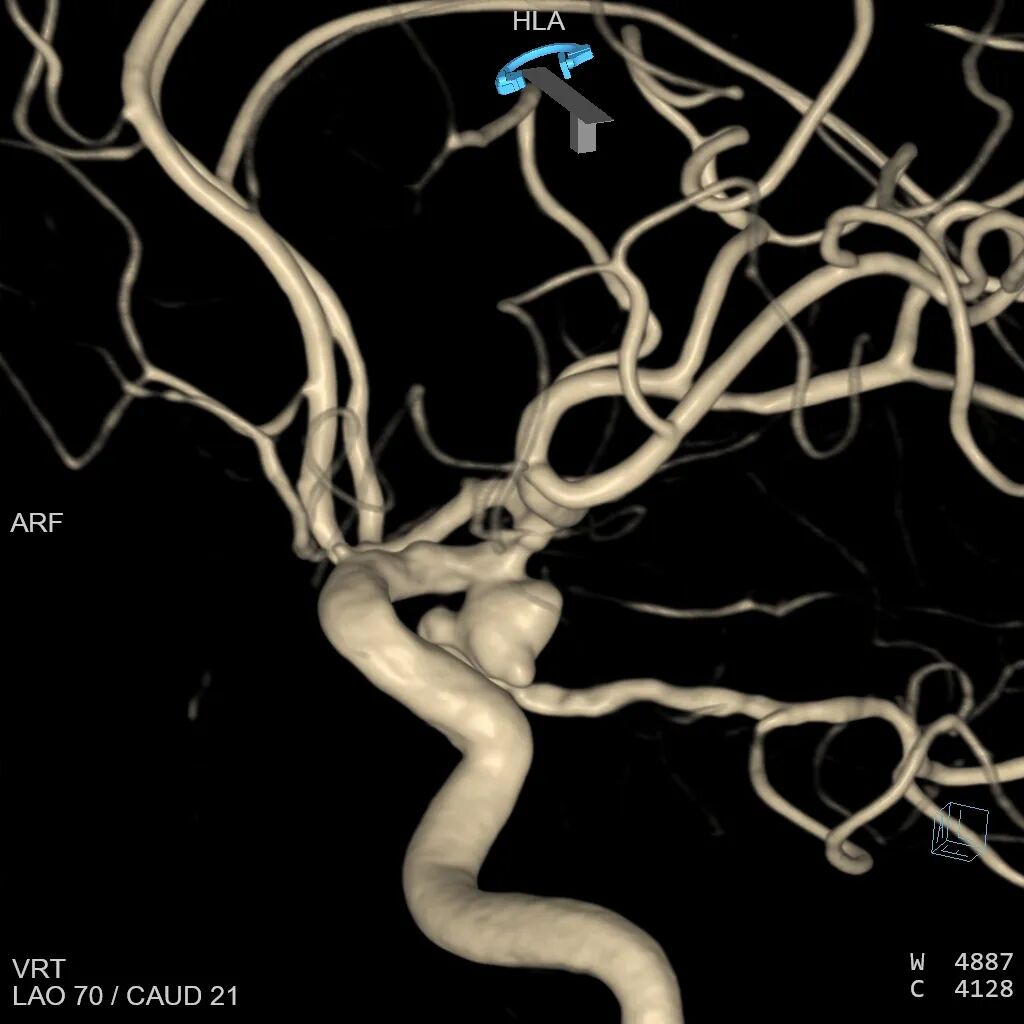

左侧颈内动脉3D造影可见动脉瘤位于后交通动脉起始处。

3D血管造影可见左侧后交通动脉瘤,大小约7.05×7.47mm,瘤颈3.68mm,考虑胚胎型大脑后动脉。

3D血管造影,选择合适的工作角度:分析载瘤动脉与动脉瘤之间的关系,动脉瘤完全由后交通动脉发出,且后交通动脉从颈内动脉处折返发出,微导丝超选进入后交通动脉角度刁钻,再次向患者家属交代病情,建议开颅夹闭,患者家属理解介入手术困难,仍要求介入治疗。

观察动脉瘤与载流动脉不同角度。